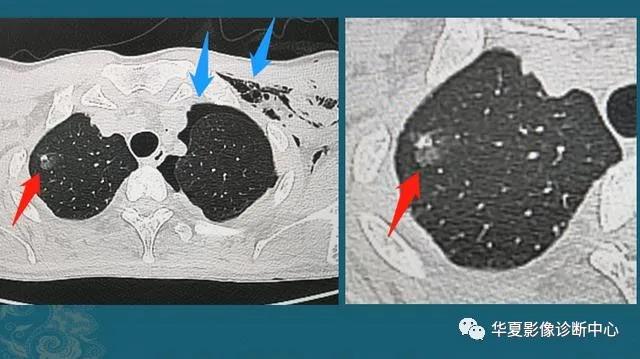

下图是一位30岁年轻人,车祸外伤,撞断3根肋骨,并造成肺挫伤、出血(创伤性湿肺):

红箭头这里的一小片肺组织被车祸撞击暴力撕裂,小血管破裂出血,形成不均匀的高密度影;蓝箭头是气胸和皮下气肿(肺破了,肺里空气溢出到胸腔和肌肉间隙内)。

这种程度的创伤没有生命危险,保守治疗1周出院了,后来小伙子复查CT,肺里留下了一个3mm的光滑小结节:

这是个良性实性小结节,是血肿吸收不彻底形成的,不要紧,不需要定期复查。